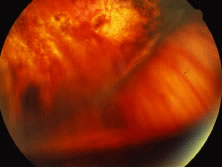

A variable number of eyes, up to 75%, develop retinal detachments (Fig. 5). Prophylactic laser for demarcating the areas of active retinitis from normal retina has been advocated to create chorioretinal adhesions that prevent retinal detachments around sites of retinal break formation (which usually occur at the zone between affected and healthy retina). Han and associates43 reported five cases treated with prophylactic laserpexy in addition to antiviral, steroid, and antiplatelet therapy. After 15 months of follow-up, no retinal detachments were noted. Sternberg and coworkers44 described a 75% decrease in the rate of retinal detachment using prophylactic photocoagulation. Some have advocated the creation of a “new ora serrata” by applying confluent rows of laser burns posterior to the areas of retinitis. However, if traction forces from vitreous organization, epiretinal membrane (ERM) formation, or proliferative vitreoretinopathy develop as they commonly do, the contractile forces will be able to overcome any increased chorioretinal adhesion created by the laserpexy. However, McDonald and associates45 reported failure of prophylactic peripheral laserpexy to prevent retinal detachment in ARN patients. In addition, many cases of ARN result in a severe vitritis, limiting the view for a planned laserpexy (Fig. 6). Therefore, vitrectomy with endolaser and concomitant encircling of the eye with a scleral buckle to reduce traction may be required in some patients.46,47 Decisions relating to the need for scleral buckling to support retinal breaks and the use of silicone oil or long-acting gases to repair retinal detachments should be made by an experienced vitreoretinal surgeon.40,48 Selection of cases to undergo operation should be made with consideration given to optic nerve function, visual potential, and medical control of retinitis.

Fig. 5. A patient with funnel-shaped retinal detachment and proliferative vitreoretinopathy complicating acute retinal necrosis syndrome.